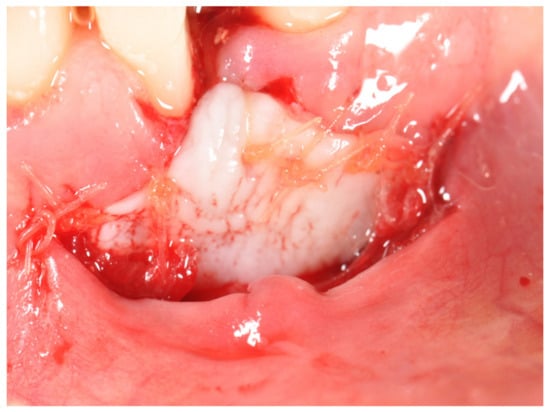

- Using a #15 blade, an intrasulcular incision was made and a partial thickness flap was raised. The recipient site was prepared by sharp dissection to create a bleeding periosteal bed free of all muscle attachments;

- The resulting flap was excised or sutured at the base of the newly created vestibule with 5-0 plain gut T-mattress sutures (Ethicon, LLC—Johnson and Johnson Co., Guaynabo, Puerto Rico).

- The graft was sutured over the recipient bed with 5-0 absorbable interrupted single sutures (Plain Gut Ethicon, LLC—Johnson and Johnson Co., Guaynabo, Puerto Rico). Where necessary, one or more cross-horizontal mattress sutures were used to ensure the complete stabilization of the graft. The area was then covered with oxidized regenerated cellulose (Tabotamp Ethicon, LLC, city, Johnson and Johnson Co., Guaynabo, Puerto Rico), adhesive dry foil (Burlew Dryfoil Jelenko, Armonk, NY, USA) and periodontal dressing (Coe Pak GC America Inc., Alsip, IL, USA);